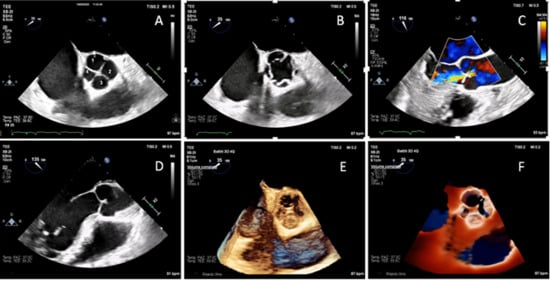

It is with great pleasure that I invite you to submit articles for the “Interesting images” Special Collection. Since we introduced Interesting Images as an article type in Diagnostics, it has served as a valuable resource for the imaging community. Many have relayed that they use these image-based case reports when encountering challenging cases or images of diseases rarely seen. Further, pitfalls are covered by this type of article and may be helpful both for experienced and less experienced image readers in making a correct evaluation.

The interesting Images together serve as a live imaging atlas covering PET, CT, MRI, and other imaging modalities. Therefore, the more cases we publish, the more likely it is that image interpreters with a difficult case can be supported by previously published cases. Although focus until now has largely been on clinical cases, it should be noted that nonclinical cases are also welcome, e.g., from preclinical in vivo imaging, including optical imaging as well as histology images from pathology.